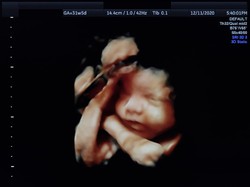

Viral seorang bayi di Lombok terlahir seperti memiliki enam kaki. Dalam istilah medis, bayi tersebut mengalami parasitic ischiopagus conjoined twin.